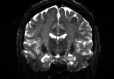

Figure 6: Example field maps (Subject ID 826353) at initialization (top row) and after optimization with Gauss-Newton (bottom row). The first column uses the proposed optimal transport initialization scheme. The middle column uses the same scheme with an additional Gaussian blur to promote smoothness. The right column uses the coarse-to-fine multilevel initialization scheme from HySCO with five levels, and the final field map is optimized at the original image resolution. The multilevel initialized field map is smooth by construction and further optimized to improve the relative image distance at the full resolution. The optimal transport initialization accurately corrects the distortions but is not smooth in the non-distortion dimensions unless blurred with a Gaussian. After the fine-level optimization all field maps are visually similar.

We compare the results of PyHySCO using our optimal transport initialization to those of the multi-level initialization used in HySCO [Ruthotto et al., 2013] both at initialization and after optimization with Gauss-Newton. The multi-level optimization of HySCO solves the optimization problem on a coarse grid and uses the result as the initialization of optimization on a finer grid, continuing until reaching the original image resolution; this follows the guidelines of [Modersitzki, 2009, Chapter 9.4]. In our experiments, we use five levels in the initialization. The multi-level initialization gives a field map that is smooth by construction and improves the distance reduction as the grid becomes more fine. The field map from the PyHySCO optimal transport initialization drastically lowers the relative error between the input images, a relative improvement of over 96% on real data and 94% on simulated data. However, the parallelized one-dimensional computations lead to a lack of smoothness in the resulting field map. The smoothness can be improved by applying a Gaussian blur to the field map from the optimal transport initialization. This field map is smoother after initialization and gives a smoother field map after optimization. These results are comparable in relative error and smoothness to the field map optimized from the multilevel initialization of HySCO. Our one-dimensional parallelized optimal transport, even with the additional Gaussian blur, is much faster to compute than the multilevel initial field map given the ability to parallelize computations. PyHySCO initialization on a GPU with the additional blur takes less than 1 second on real data and about 3 seconds on simulated data. In comparison, the multi-level initialization on a CPU takes 30 to 40 seconds on real data and over 2 minutes on simulated data. The mean and standard deviation relative improvement, smoothness value, loss function value, and runtime are reported in Table 2 across all datasets. Examples of these field maps before and after optimization are shown in Figure 6.